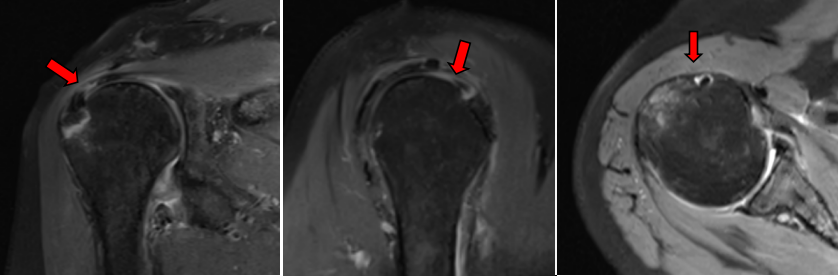

王某某,女,61岁,3个月前因摔伤致右肩部肿痛伴功能受限,于当地医院住院1周后因右肩部疼痛加重伴活动受限来我院就诊。行右肩MRI检查示:右肱骨大结节骨折,伴冈上肌腱部分撕裂、肩胛下肌腱损伤、肱二头长头肌腱炎、关节囊粘连。

4. 关节镜下关节囊松解、肩峰成形、单排铆钉改良Mason-Allen缝合。